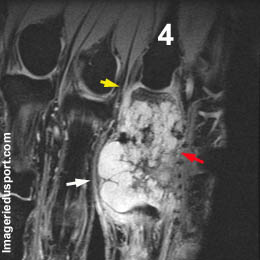

B - IRM coupe sagittale T1 gado fat-sat de D4 : Aspect hétérogéne. Extension extra-osseuse refoulant les tendons avoisinants (flèches rouges). Zones nécrotiques (flèches blanches) ne prenant pas le contraste. A noter, la présence d'un hypersignal et donc d'une prise de contraste de la base de la phalange moyenne et proximale (flèches jaunes)

Chondrosarcome de la phalange proximale du 4eme rayon droit